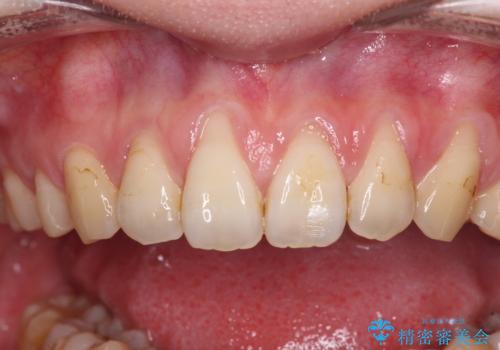

- 他院で矯正治療を終えた結果、上顎前歯の歯肉が退縮してしまい、根が見えていることが気になるとのことで来院された患者様です。

歯肉退縮に対して、上顎からの結合組織移植術(CTG)により、歯根の被覆を行うとともに、歯肉の厚みを増すことで将来の退縮リスクを抑制することとしました。

抜歯矯正を行ったため、採取可能な歯肉の量が少なくなるため、被覆量が不十分の場合には、追加で手術を行うことで患者様の了解を得ました。